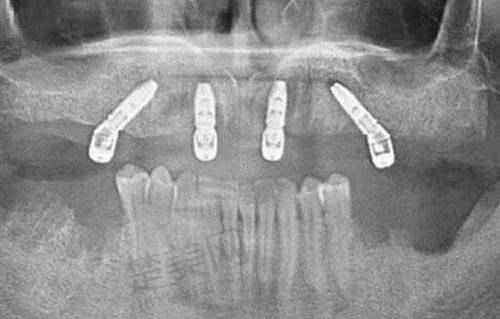

私立机构常先引进数字化设备,如3D口扫、种植导板导航系统。有数据显示,2022年国内90%的民营口腔机构已配备数字化诊疗设备,而国有医院占比约65%。西安团圆口腔医院就引进了3D数字化中 心等设备,这些设备不仅提高了治疗的精细度,也大大提升了患者的就诊体验。比如在种植牙手术中,3D口扫可以快速、正确地获取患者口腔的三维数据,医生根据这些数据制定更精细的种植方案,种植导板导航系统能帮助医生在手术中更严谨地植入种植体,提高手术的成功几率和安心性。